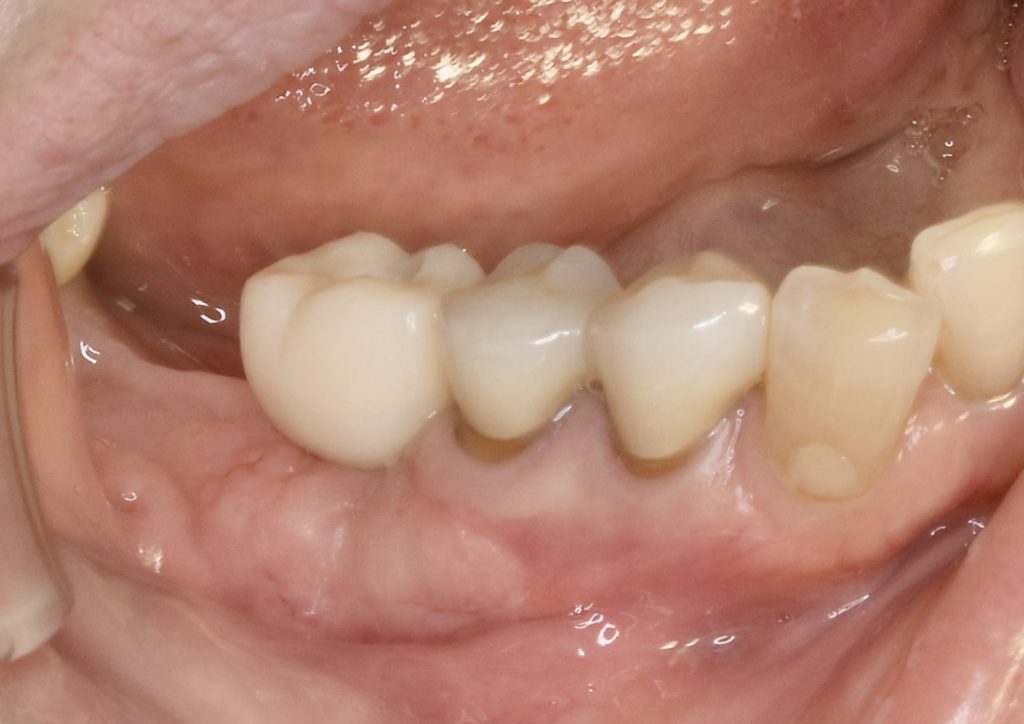

下記の症例はインプラントだけ埋入すれば良いわけではありません。

周囲環境を整え長期的に安定し、長持ちさせるインプラントを目指す必要があります。

その為に歯肉を移植しインプラント周囲に強い抵抗力を持つ歯肉を作る事が大切です。

遊離歯肉移植術にかかる費用 約121000円(税込)